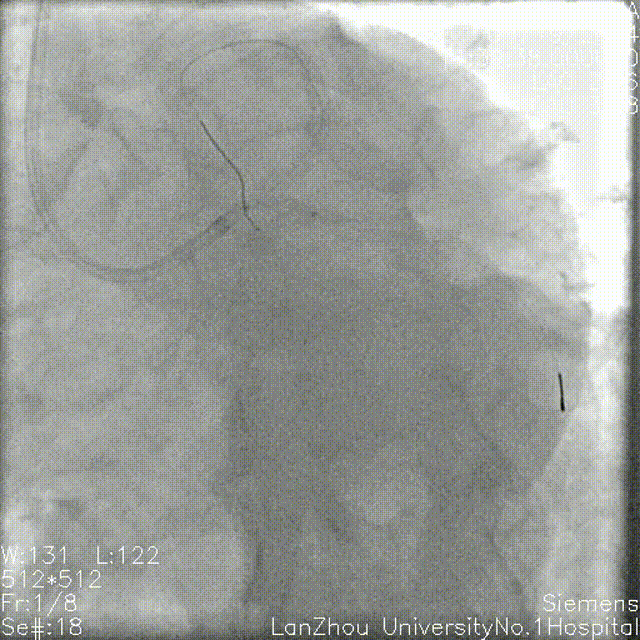

复查造影后再次复查前降支IVUS

前降支近中段支架膨胀不全;

遂3.5mm球囊高压扩张;

结合术后IVUS,考虑该处钙化严重及钙化小结导致IVUS导管及球囊无法通过。

复查造影支架贴壁良好